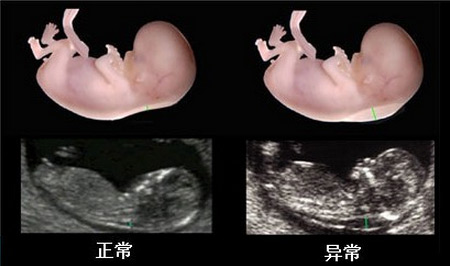

NT(nuchal translucency),颈项透明层,指胎儿颈后冠状切面皮肤至皮下软组织之间的最大厚度,是由胎儿生理性新陈代谢所产生的液体积存形成。正常胚胎发育过程中,颈部淋巴管与颈静脉窦在11~14 周左右相通,在相通之前,少量淋巴液积聚在颈部形成颈项透明层,超声表现为胎儿正中矢状切颈项后的带状无回声。

颈项透明层增厚与胎儿异常的关系十分密切,颈项透明层增厚提示胎儿异常的可能。颈项透明层增厚越明显,胎儿异常机会就越高,异常程度也越严重。

有研究发现,颈项透明层增厚在3mm时,90%为正常胎儿,10%为异常胎儿;而颈项透明层增厚达到6mm时,90%为异常胎儿。这些异常中包括染色体非整倍体异常,如2l-三体、18-三体和x单体(45,X0),另外还有13-三体、15-三体、三倍体等;还包括非染色体异常的严重畸形及罕见综合征,例如露脑畸形或无脑儿、脑膨出、全前脑、脊柱裂、严重心脏畸形、某些膈疝、脐膨出、腹裂、多囊泡肾、胎儿型多囊肾、肾缺如、巨膀胱、体蒂异常、致死性骨骼畸形以及部分骨骼肌肉异常等等。